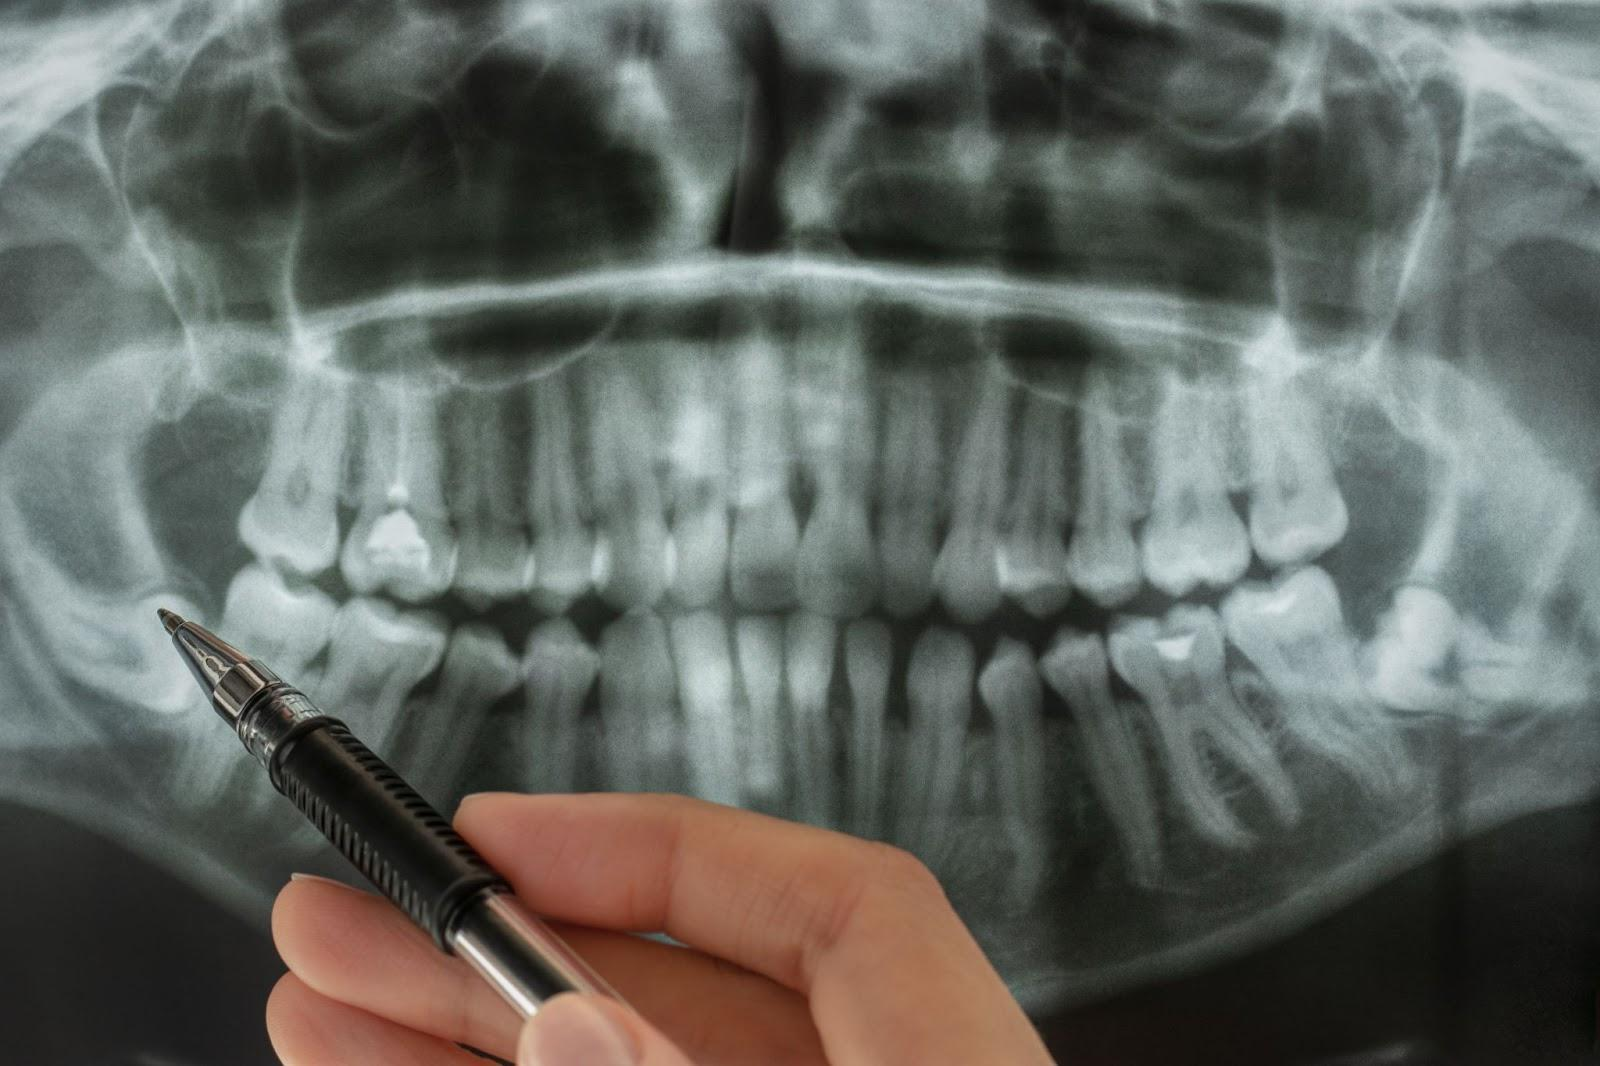

CTを使うと、歯の根の長さや本数を正確に把握できます。

特に根管治療では、根の形や長さを正しく知ることが非常に重要です。

根の長さを誤って治療してしまうと、器具が根の先を突き破り、炎症や痛みを引き起こすこともあります。

CTで事前に根の構造を把握しておくことで、そうしたリスクを減らし、より精密で安全な治療が行えます。